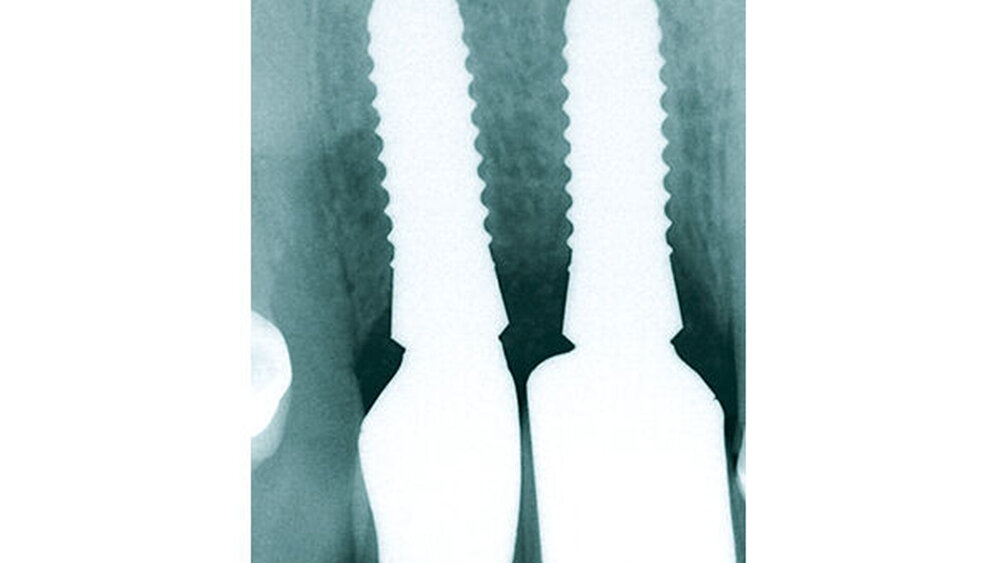

Die Implantatschulter wurde leicht supracrestal platziert, sodass die prothetische Plattform zirka 2 mm unter dem Weichgewebeniveau zu liegen kam (Abb. 5). Lateral der Implantatschulter wurden die autologen Knochenspäne gemischt mit feinkörnigem BioOss (Geistlich) eingebracht und die Implantate über den Klickmechanismus in der Innenkonfiguration des Implantats mit der PEEK-Abdeckkappe verschlossen (Abb. 6). Die CERALOG Hexalobe-Implantate sind im Halsbereich weniger rau als im enossalen Bereich, damit sich das Weichgewebe im Bereich des Implantathalses und die Knochenzellen an der mikrorauen Struktur im enossalen Bereich optimal anlagern können. Das Augmentat wurde mit einer Bio-Gide-Membran (Geistlich) abgedeckt. Es lag ausreichend keratinisierte Gingiva vor, sodass keine Weichgewebeverdickung erforderlich war. Der Wundverschluss erfolgte ohne Periostschlitzung (Abb. 7), um die Ernährungsphysiologie des Weichgewebes nicht zu verschlechtern und eine Verschiebung der Mukogingivalgrenzlinie nach koronal zu vermeiden. Der Lappen ließ sich für den spannungsfreien Wundverschluss tunnelierend ausreichend weit nach subnasal präparieren. Im Anschluss an die Implantatinsertion wurde die Valplast-Prothese basal ausgeschliffen, um augmentationsbedingte Druckstellen zu vermeiden. Die postoperative Röntgenkontrolle (Abb. 8) zeigt eine anatomisch exakte Implantatpositionierung nach Schablonenvorgabe.

Während der komplikationslosen Heilungsphase betreute der Hauszahnarzt den Patienten. Wie geplant, erfolgte nach zwölf Wochen die Implantatfreilegung (Abb. 9) in unserer Praxis. Das Weichgewebe zeigte sich in einem blutungs- und reizfreien Zustand. Mit einer leicht palatinal orientierten crestalen Kieferkammschnittführung wurden die Implantate freigelegt, das Weichgewebe wurde nach vestibulär verdrängt (Abb. 10) und die Gingivaformer wurden aufgesetzt. Um einen quantitativen Zugewinn von keratinisiertem Gewebe zu erhalten, wurde die Naht zwischen den Implantaten nicht komplett geschlossen. Die Implantate zeigten sich klinisch und röntgenologisch sicher osseointegriert (Abb. 11).

Drei Monate nach Einsetzen der definitiven Kronen erschien der Patient zur finalen Kontrolle in unserer Sprechstunde. Die keramischen Kronen (Cercon Ceram Kiss, Degudent) sind auf individuellen CAD/CAM-gefertigten Abutments (DEDICAM, CAMLOG) zementiert (Ketac Cem). Die Röntgenaufnahme zeigte osseointegrierte Implantate mit gesunder Knochenstruktur und im periimplantären Bereich keine überschüssigen Zement‧reste (Abb. 12). Die Kronen fügen sich in Form und Farbe natürlich in die Zahnreihe ein (Abb. 13). Das Emergenzprofil zwischen 13 und 12 ist aus unserer Sicht suboptimal, jedoch bei tiefer Lachlinie für den Patienten nicht relevant. Dieser ist mit seiner metallfreien Versorgung sehr zufrieden.